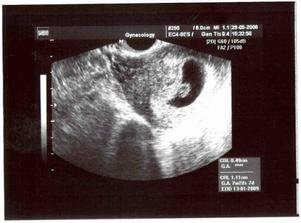

29.5. mi paní doktorka potvrdila, co už jsme samozřejmě dávno věděli a ukázala mi naše embryjko na ultrazvuku, kde mu krásně tikalo srdíčko a mělo celých 1,11 cm...no prostě jednička. Bylo to krásný 🙂